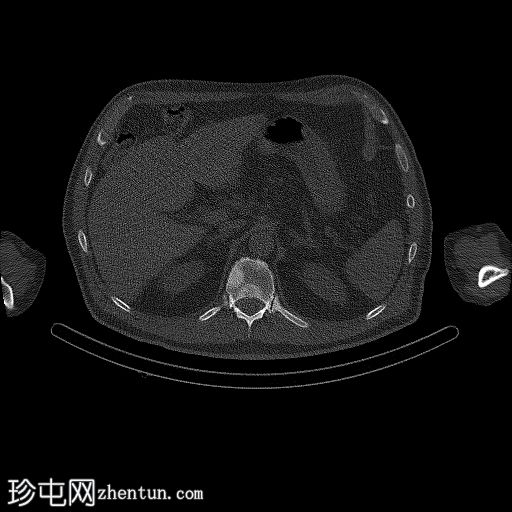

轴位

SPECT-CT

脊柱、肋骨、骨盆、颅骨、肩胛骨、胸骨、左侧肱骨和双侧股骨干可见多处放射性示踪剂摄取异常增高,与SPECT-CT扫描图像上显示的硬化病灶相对应。双肾未见放射性示踪剂活性。

骨骼内多处局灶性放射性示踪剂摄取增高,符合骨转移;肾脏内无放射性示踪剂活性,与超扫描结果一致。